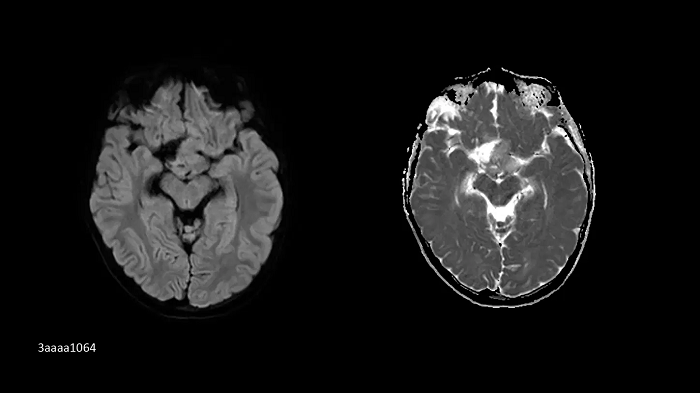

SMS RESOLVE

Exceptional diagnostic performance with RESOLVE using high-resolution DWI and DTI of the brain, as well as increased efficiency with Simultaneous Multi-Slice (SMS).

PAT 2 SMS 2, b1000| 1.0 × 1.0 × 4.0 mm3 | TA 2:32 minutes